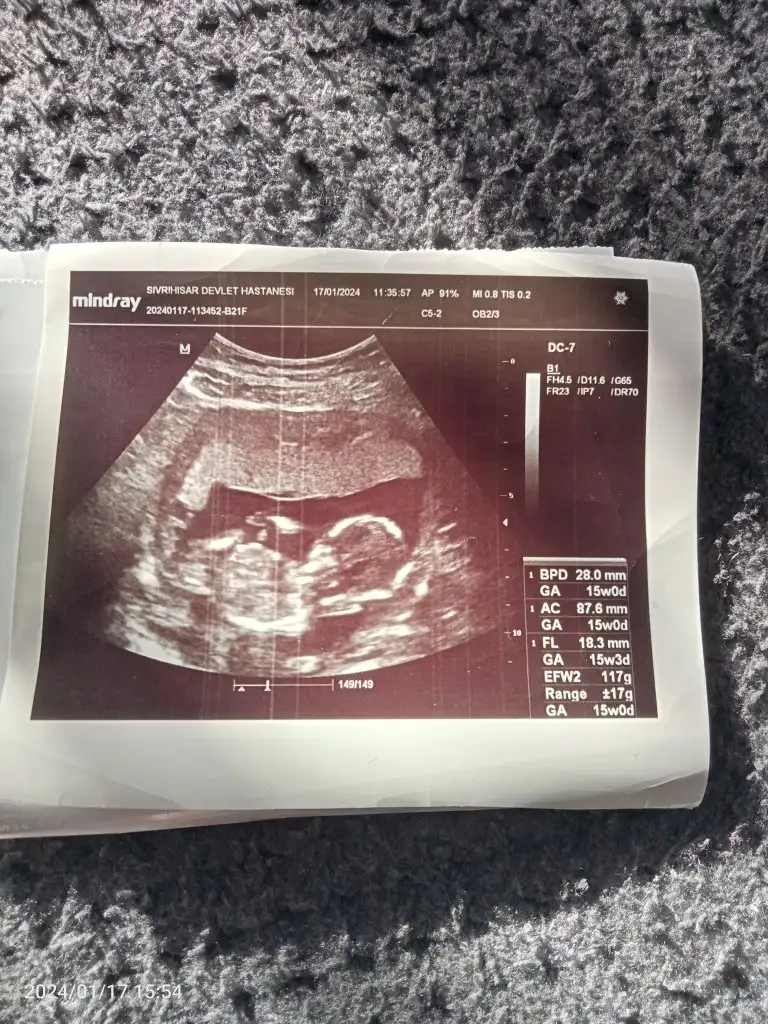

daha erken gibi canım eğer bacak kısmının oldugu ultrason varsa daha iyi olurKızlar benim bebişim kız mı erkek mi sizce![]()

Yok canım yadaha erken gibi canım eğer bacak kısmının oldugu ultrason varsa daha iyi olur